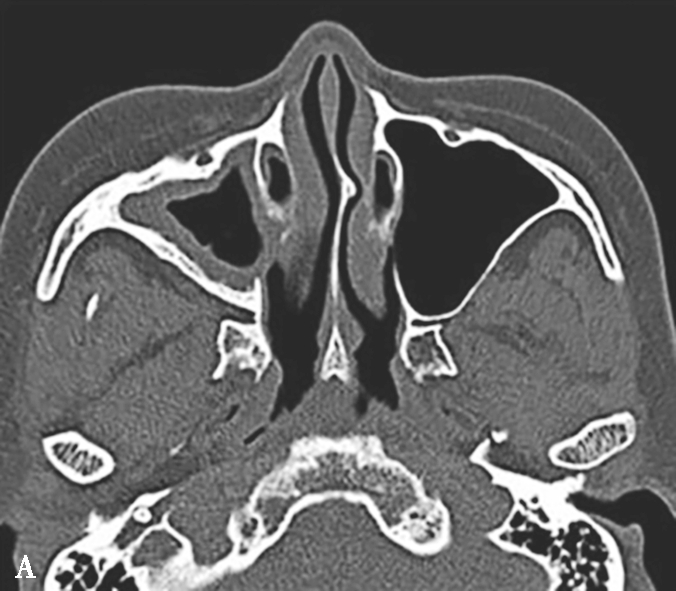

图1-3-19 急性鼻窦炎

A.CT横断面骨窗,示右侧上颌窦内软组织密度影,可见气-液平面;B、C.横断面及冠状面骨窗,示右侧上颌窦黏膜增厚